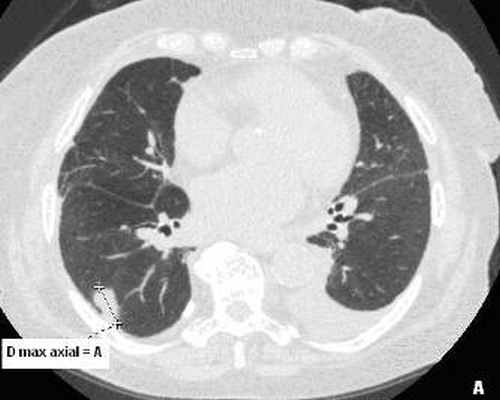

При проведении КТВР для оценки природы консолидаций на фоне ДИЗЛ выполнялось построение мультипланарных реконструкций (МПР) с расчетом 3 D -коэффициента. Расчет 3 D -коэффициента проводился для оценки формы и изменения пространственной конфигурации консолидации при МПР. Для вычисления 3 D -коэффициента использовалась формула:

3 D -коэффициент – объемный коэффициент,

D max axial – максимальный диаметр консолидации на аксиальных срезах,

D min coronar – минимальный диаметр консолидации на МПР в коронарной плоскости.